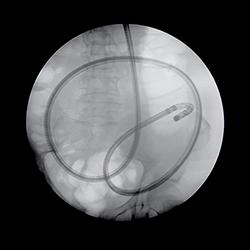

И именно в таких случаях помочь гастроэнтерологу и хирургу призвана еще более современная методика — двухбаллонная энтероскопия, называемая на Запа-

де еще «Push-and-Pull-Enteroskopie» (PPE). Уже из названия становится понятным и сам принцип этого предложенного в 2001 г. японцами (Yamamoto H. et al., 2001) и впервые в 2003 г. примененного на Западе исследования. Передвижение по тонкому кишечнику телескопически выдвигаемого зонда длиной около двух метров, состоящего из непосредственно энтероскопа и наружного зонда большего диаметра, осуществляется путем «нанизывания» на эндоскоп кишки, что становится возможным за счет периодического раздувания и перемещения относительно друг друга двух баллонов, один из которых находится непосредственно на конце эндоскопа, а другой — на конце наружного зонда. Так как по структуре своей двухбаллонный энтероскоп является обычным эндоскопом, он обладает и всеми его

преимуществами — возможностью промывать оптику во время исследования (что особенно ценно при диагностике кровотечений), проводить биопсии и, самое главное, осуществлять эндоскопические вмешательства. Именно поэтому зачастую капсульная эндоскопия (естественно, при положительном результате) дополняется двухбаллонной энтероскопией. Введение энтероскопа, как правило, осуществляется перорально ортоградно, только в редких случаях (например, при недостаточной инспекции кишечника или выявленной во время капсульной эндоскопии локализации источника кровотечения в дистальных отделах тонкого кишечника) необходимо дополнительное проведение ретроградной трансанальной энтероскопии. Длительность исследования составляет в среднем два часа, естественно, без внутривенного наркоза (как правило, хватает обычной седоанальгезии) тут не обойтись.